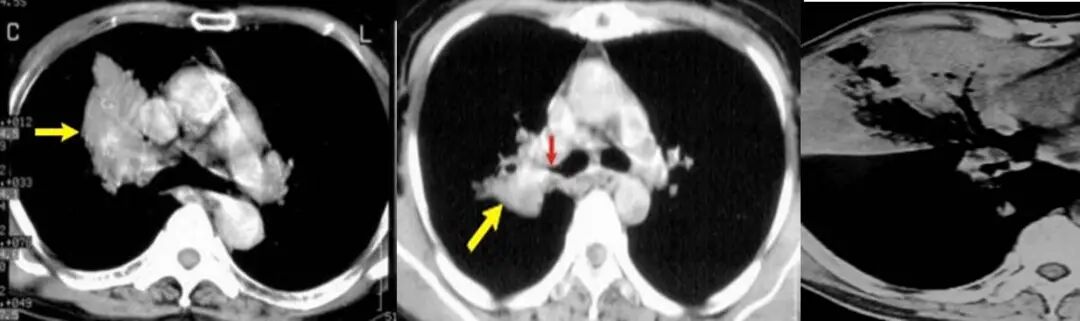

1、单一肺内病灶最主要是判断病变的性质,虽然比较像肿瘤,但仔细看病变内除了有支气管充气影,还有气泡影,病变局部边缘也有点模糊,因此这个炎症(脓肿)是有可能的,这个人肺泡灌洗出现克雷伯杆菌,结合病史那克雷伯肺炎(脓肿)是有可能的。

4、PPL 肿块型是有可能,内支气管扩张伴僵硬?

7、MALT 有可能,代谢上比较符合,病灶境界较清楚,周围还算干净,渗出不明显,支气管局部狭窄,患者无明显症状,就是 PPD 试验强阳不知怎么解释,不会是两者合并存在吧。

12、没有临床症状,单看影像,不看实验室检查结果的话,是比较像肺 MALT 的。